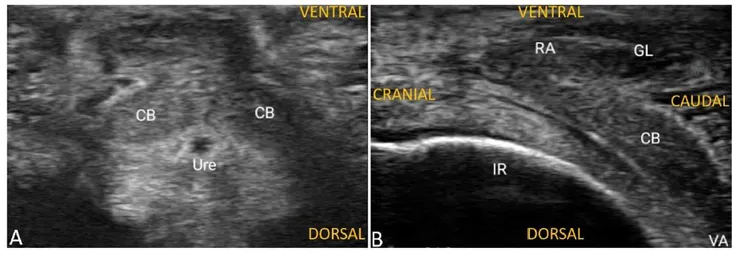

研究方法是受試者以「面對面、女性在上、坐姿」、「面對面、男性在上、女性下方墊枕頭」、「面對面、男性在上、女性下方沒有墊枕頭」、「面對面、兩人皆坐姿」、「女性跪姿、後方進入」五種體位,各進行十分鐘的性交,十分鐘一到不管「進度」如何一律停止。性交前、後各對女方陰蒂做一次都卜勒超音波,量測性交前後陰蒂的血液流量變化。

結果如下:「面對面」的四種都優於看不到臉的「女性跪姿、後方進入」,除了心理因素外,「腰的用力方向跟重力相同」,可以增加接觸時的刺激(等等這血流量該不會是因為被「打腫」的吧)。四種面對面體位中,又以「面對面、男性在上、女性下方墊枕頭」效果最佳。